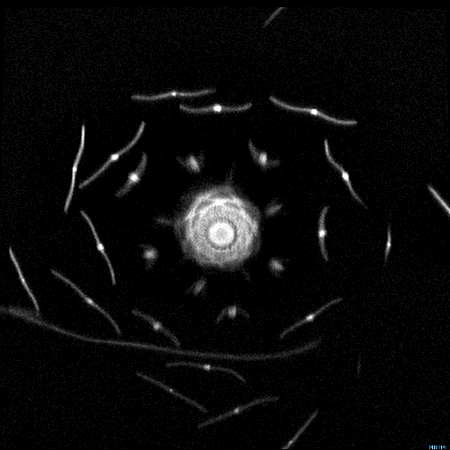

Bu hareketli MR görüntüleri şaşırtıyor - Resim: 1

Bir Tıp Mühendisi tarafından MR makinesini test etmek amaçlı kullanılan bu yöntem harika görüntüler ortaya çıkarttı.

Çanak çiçeği